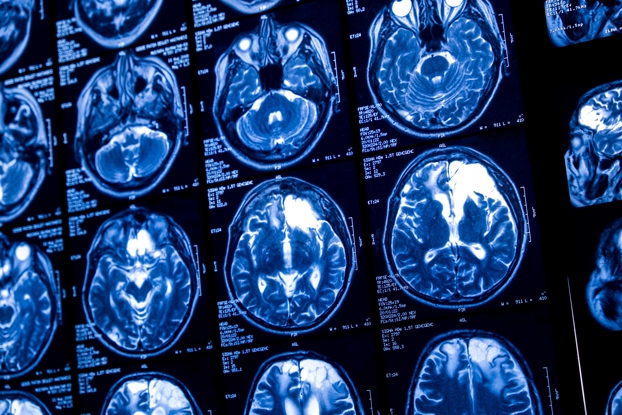

Amon Zakeri, MD – Endovascular Neurosurgery Dr. Zakeri received his undergraduate degree from The George Washington University in Washington. D.C. ...